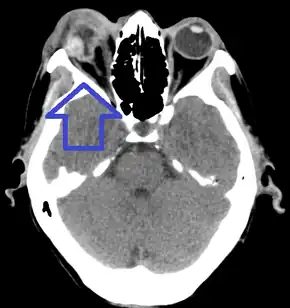

On CT scan, signs of global rupture include: deepening of the anterior chamber, alteration of global contour with scleral folds, discontinuity of scleral folds, and a shrunken globe.[6]

Globe rupture

Globe rupture with protruding uveal tissue